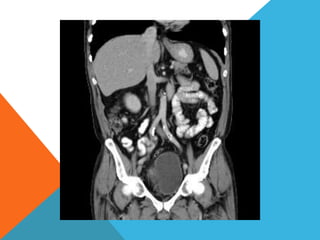

El paciente presentó síntomas de sangrado digestivo y pérdida de peso. Exámenes revelaron gastritis crónica asociada a H. pylori. Un tumor fue descubierto en una colonoscopia normal. La cirugía removió un tumor fibroide solitario, una rara neoplasia mesenquimal que usualmente crece lento y tiene bajo potencial de malignidad. El pronóstico después de la remoción quirúrgica es generalmente bueno.